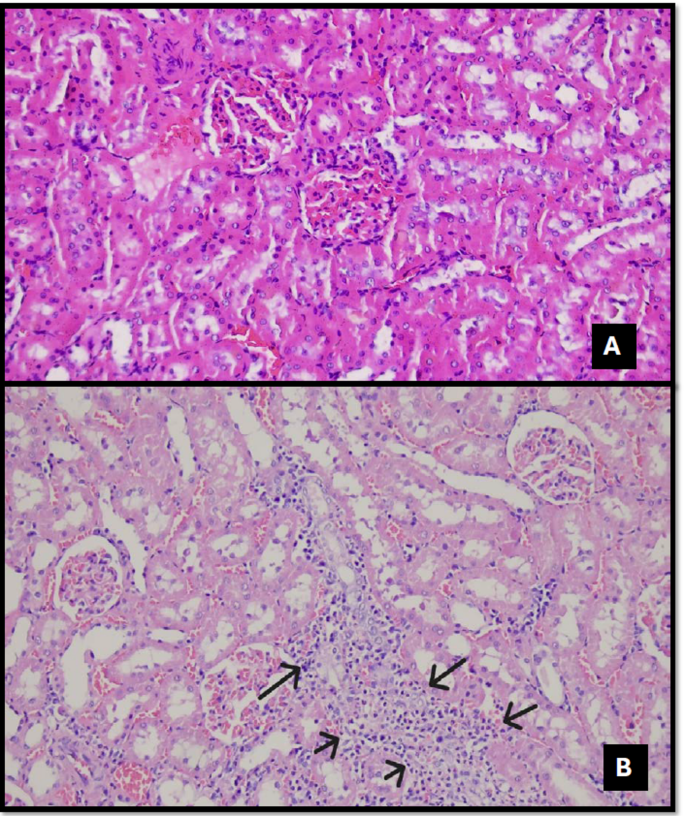

In the control group, renal structures were consistently within normal morphological limits across all histopathological examinations, with no evidence of inflammation, necrosis, or degeneration (Figs. 1, 2, 3, 4, 5, 6, 7, 8 and 9).

(A) Mild interstitial inflammation is observed. No marked signs of regeneration are present. The Bowman’s capsule space appears within normal limits. ×200. (B) Expansion of the Bowman’s capsule and foci of regeneration are evident within the area of interstitial inflammation, more prominently in the TAK + DEX group (black arrows). ×200.

Expansion of the Bowman capsule (Figs. 1 and 2) was observed in 87.5% of the TAC group and 100% of the TAC + DEX group. A statistically significant difference was detected between the groups (p = 0,003) (Table 3).

Interstitial inflammation (Fig. 6) was found in 87.5% of the TAC group and 100% of the TAC + DEX group. However, no statistically significant difference was observed between the groups (p = 0.559) (Table 3).

The presence of mitosis (Fig. 6) was recorded as 0% in the Control (SF) group, 37.5% in the DEX group, 87.5% in the TAC group, and 75% in the TAC + DEX group. This difference was also found to be statistically significant (p = 0.005) (Table 3).